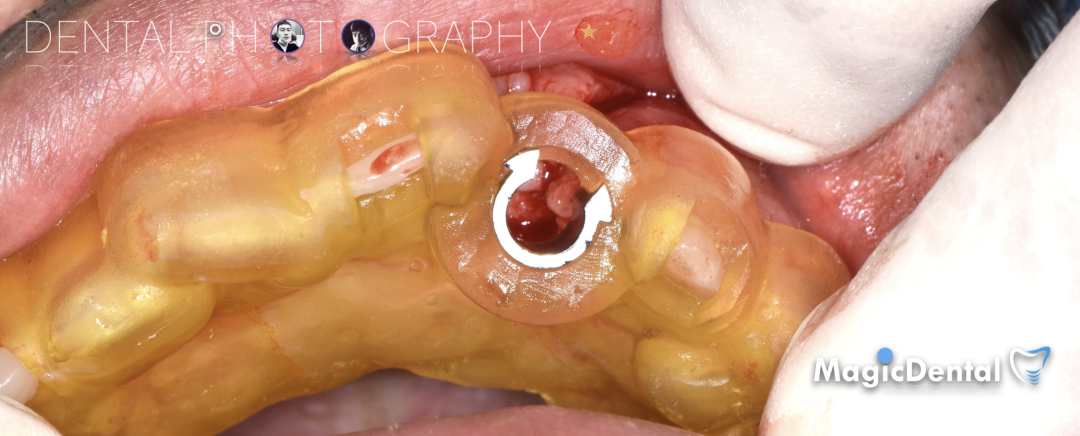

骨块细节

切开翻瓣,彻底暴露术区,试戴骨块。

调整骨块外形,适配受植区域,打开骨髓腔。

预备固位钉洞,固定骨块

骨膜减张,放置骨粉,放置骨块,钛钉固定骨块。

固定骨片,修整骨块边缘,继续放置骨粉覆盖骨块及受植区,放置骨膜,严密缝合创口。